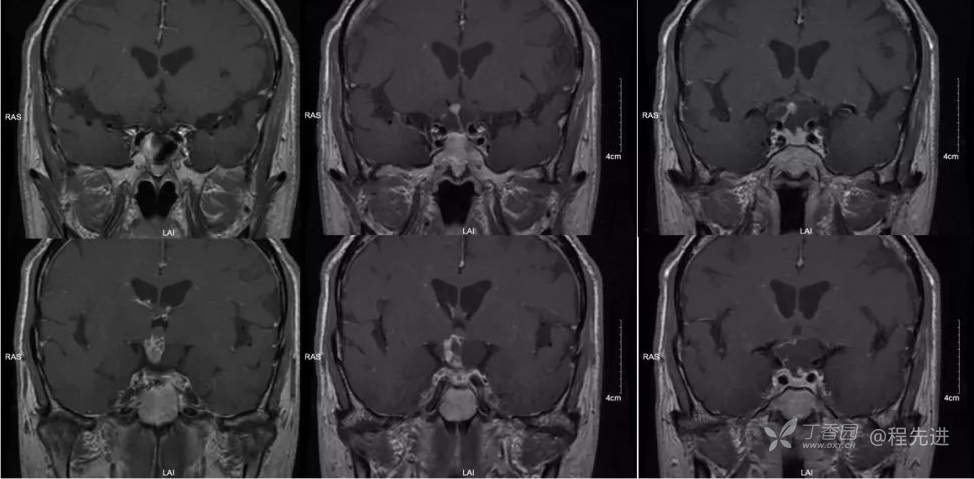

img

T1矢状位

T1增强矢状位